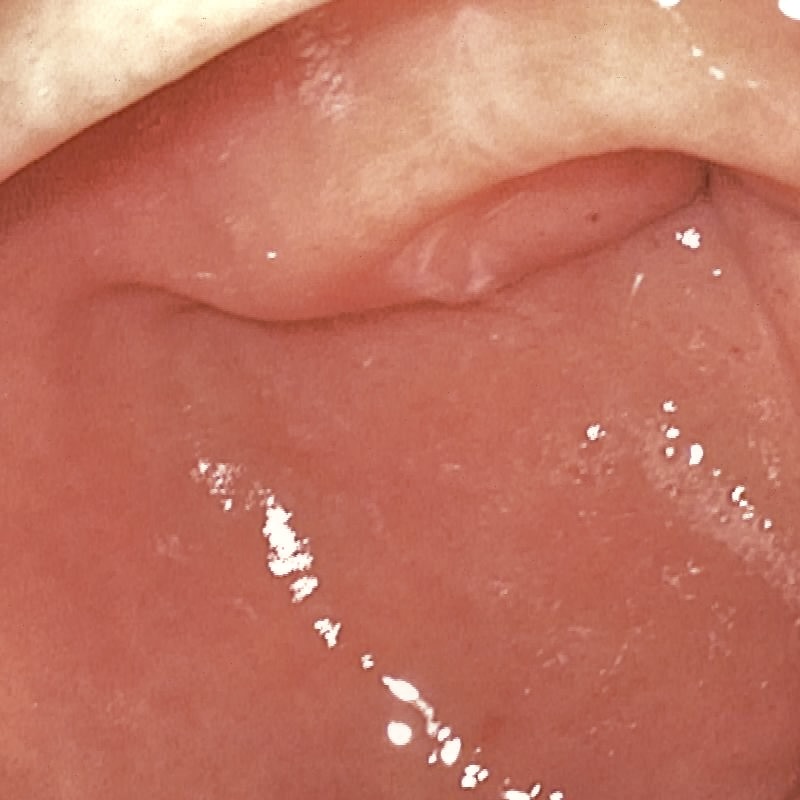

| (a) Input | (b) LIME | (c) HDRNet | (d) LECCM | (e) SwinIR | (f) NAFNet | (g) EndolMLE | (h) Ours | (i) GT |

The proposed method was evaluated on a synthetic dataset. All deep learning-based methods were fine-tuned based on E-kvasri. Figure 2 presents sample results of the proposed method and comparative methods on four endoscopic images from the E-kvasri.